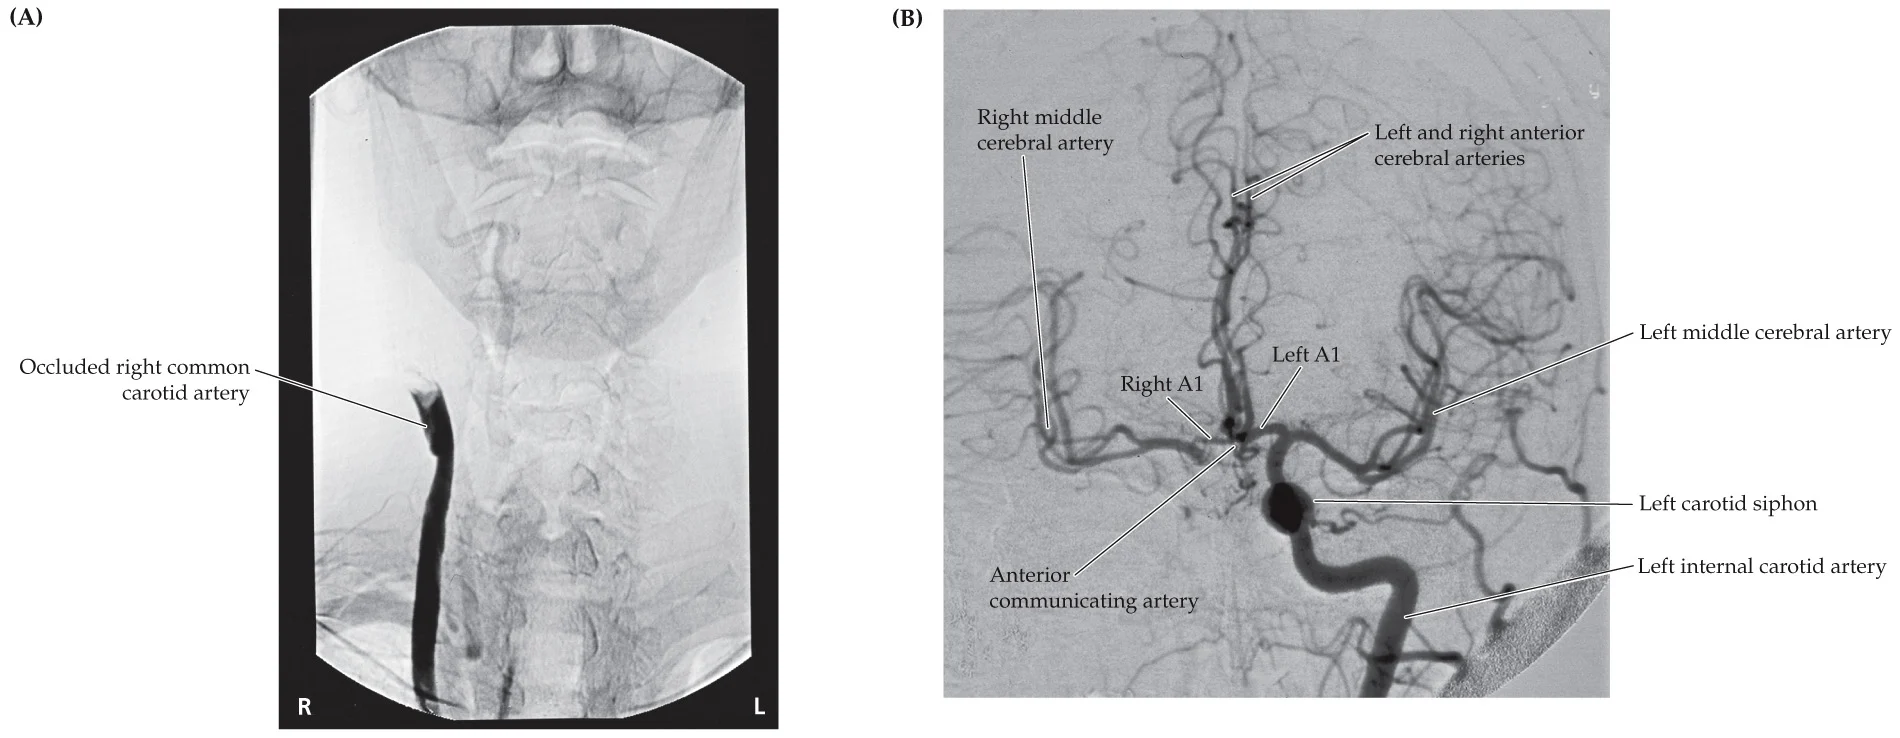

A 71-year-old right-handed man with a long history of cigarette smoking and hypertension had an episode 5 months before admission of right hand weakness and speech difficulty, “mixing up words.” Since then, he has had several episodes, lasting a few minutes each, of dim, blurry vision in the left eye. Finally, he fell on three separate occasions when his right leg suddenly gave out, most recently on the day of admission. Examination was normal except for a high-pitched bruit audible over the left carotid artery

right medial primary motor cortex, left superior MCA, left opthalmic artery